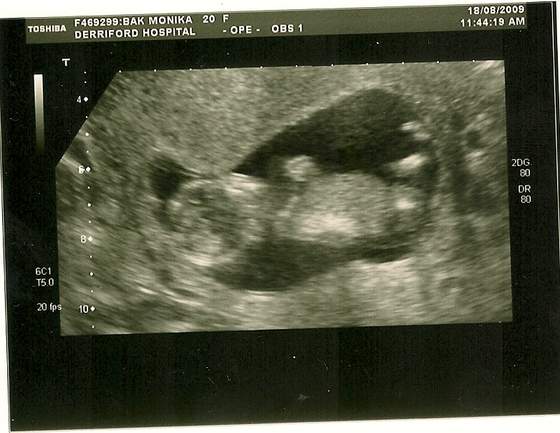

juz sie niemoge doczekac az pojdzie troszke sobie odetchne no i juz sie niemoge doczekac az bede wiedziala co mi tam za fasoleczka wyrasta odrazu tylko jak bede wiedziec zaczynam kupywac z checia bym kupila juz wszystko lozeczko wozek ubranka doslowanie wszystko ale jak to mowia z wozkiem i lozeczkiem le[piej poczekac